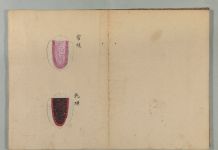

先日撮影した

写真を添えます。